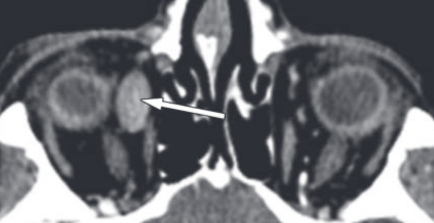

Varice Orbitaire

- Dilatation veineuse

- Augmente au Valsalva

- Proptose

- Première cause de saignement intra-orbitaire

- Peuvent se thromboser